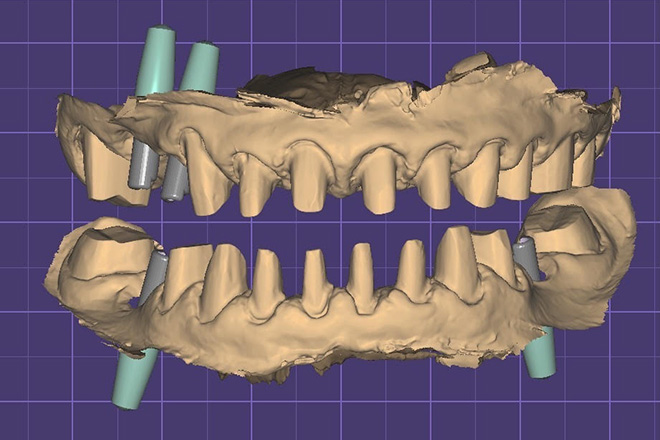

高畑先生が製作したインプラント上部構造(セラミック歯)の治療例

治療前の口腔内写真

全体的な噛み合わせが狂っている状態でした。

全顎治療(フルマウス治療)で理想的な噛み合わせを再建していきます。

治療中のデジタルデータ

治療後のレントゲン写真

治療後の口腔内写真

患者様は50代女性、治療期間は1年。